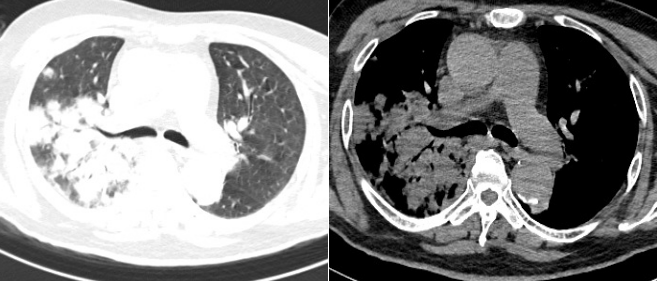

5月14日和5月20日复查胸片(图17)

17  复查胸片